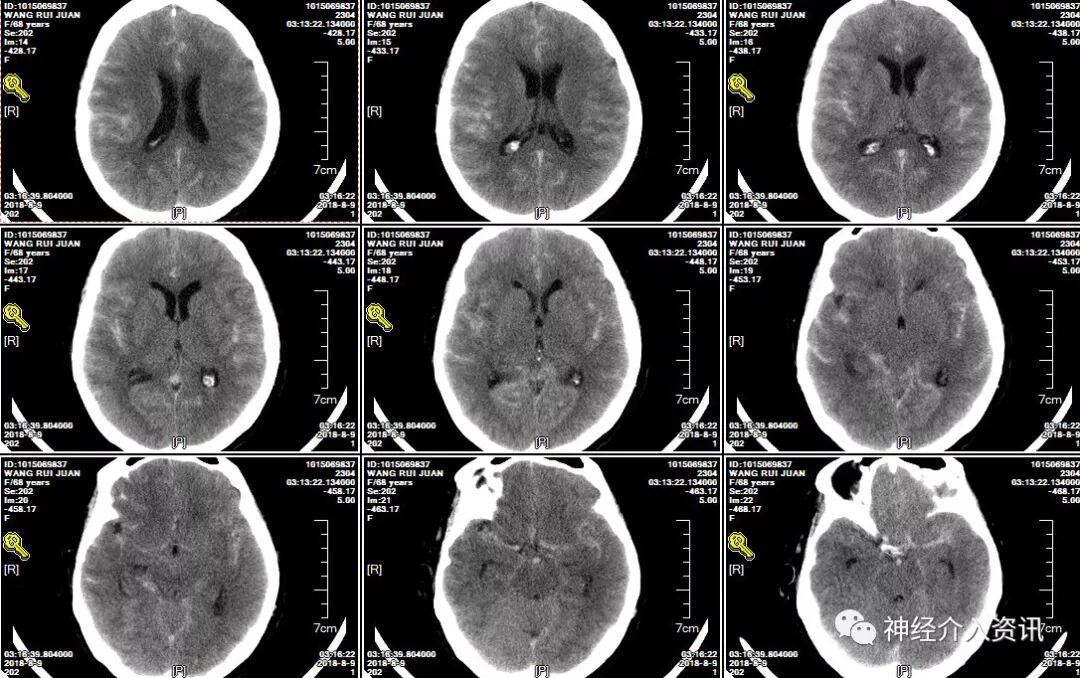

先处理大脑中动脉分叉部动脉瘤,应用Echelon-10微导管在微导丝导引下置于动脉瘤的中心,将支架导管置入同侧大脑中动脉M2中,释放4*15mm Solitaire™ AB支架一枚,跨越动脉瘤颈,应用Axium™ Prime ES 1.5mm*3cm弹簧圈及1mm*3cm弹簧圈将大脑中动脉动脉瘤致密填塞,在栓塞过程中微导管始终保持稳定,弹簧圈顺利推送无顶管现象,完成对该动脉瘤的栓塞;继续处理右脉络膜前动脉动脉瘤, Echelon 10在微导丝导引下置于动脉瘤的中心,释放3.5*15mm支架一枚,跨越动脉瘤颈,应用一枚Axium™ Prime ES 1mm*3cm弹簧圈将动脉瘤致密填塞,完成对两个动脉瘤的栓塞。

图四 黄箭头显示应用一枚Axium™ Prime ES 1mm*3cm弹簧圈将脉络膜前动脉动脉瘤致密栓塞,脉络膜前动脉保存良好(红箭头)